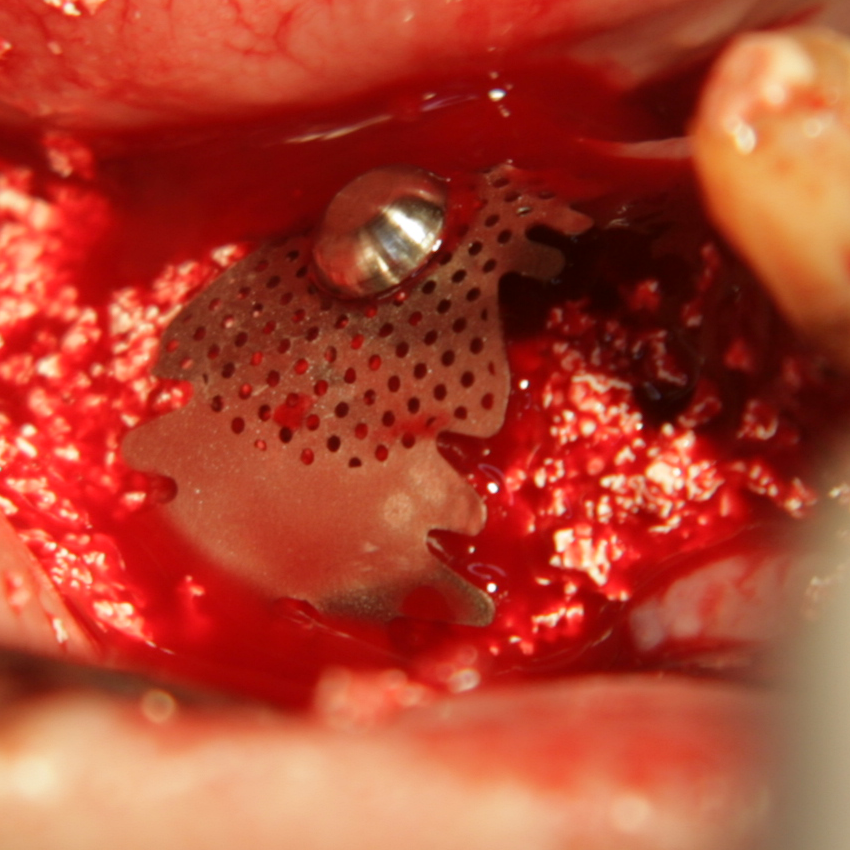

Титановите мембрани са твърди, ригидни приспособления, които се поставят в участъци с необходимост от увеличаване на костния обем - най-вече в областта на имплантологията, но също при радикуларни кисти и много рядко след екстракция на ретинирани мъдреци, при дефкетни фрактури, пострезекционни дефекти на челюстите, тежки остеомиелити и специфични възпаления на костта. Идеята на титановата мембрана е да предпази меките тъкани от колапс, поне за известен период от време, през който период под мембраната да започне костообразуване. През първите шест - осем месеца титановата мембрана оказва своя ефект, след което вече е безсмислено да остава в устата на пациента.

При операции с цел изграждане на допълнителн костна тъкан (костна пластика) винаги е добре да се перфорира кортикалната пластинка на костта. През тези перфорации излизат костни клетки, които постепенно прорастват в котозаместващия материал и синтезират нова костна тъкан. Перфорациите могат да се извършат с кръгло борче или с АСМ - фрезата на Neobiotech - Южна Корея.

С фрезата за автогенна кост се извършва много бързо и лесно отнемане на

кортикалната кост

Автогенна кост

Tent screw - винтове за

фиксиране на титановата мрежа

Около винтовете се поставя костозаместител, добре е да се размеси с

автогенна кост

Титанова мембрана

PRF